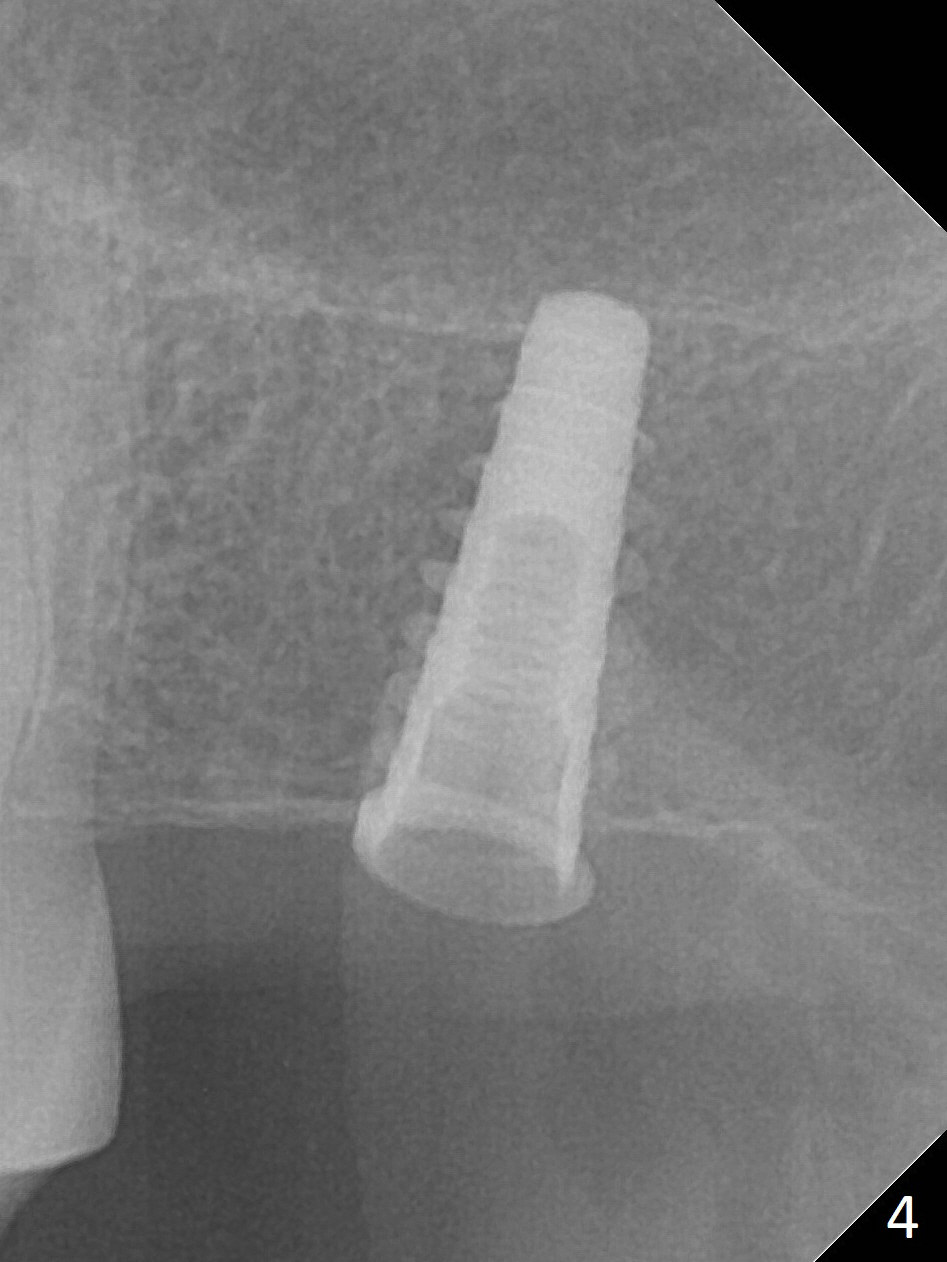

The ridge is pointed at the site of #15 (Fig.1). A 1.2 mm initial drill is used to start osteotomy for 10 mm, followed by an incision over the ridge mesiodistally for ~ 8 mm. After tapping the #15 C blade, the 1st Bone Expander 1.0/1.6 mm) is inserted for ~ 11 mm (Fig.2, 20 Ncm). Bone expansion continues until #4 Expander (2.4/3.7 mm, Fig.3). When 4x11 mm and 4.5x11 mm dummy implants are placed (Fig.4), insertion torque remains 20 Ncm. Following placing allograft with 3-4 amalgam carriers, a 5x11 mm IBS implant is placed with 20 Ncm (Fig.5,6). In fact the implant turns when an abutment is placed. When the implant is re-inserted, torque decreases to 10 Ncm. Instead a healing screw is placed. The low torque value is due to soft bone and failure to underprep. #4 Expander (Fig.3) seems larger than 4.5 mm implant (Fig.4). #3 Expander (1.7/3.1 mm) should have been used prior to definitive implant placement. The implant appears to have osteointegrated 3 months postop (Fig.7); impression is taken. The bone density at the crest increases 1.5 years post cementation (Fig.8 *, as compared to Fig.6), although there is mild bone loss. Implant placement should be deep when bone expansion is carried out. The tooth #14 develops a buccal fistula, corresponding to periapical radiolucency of the mesiobuccal root (Fig.9 white >). The abutment of #15 may be incompletely seated (black <). PA taken when RCT of #14 is finished does not show the incomplete seating of the abutment (Fig.10). Since there appears no history of abutment screw loosening, the abutment is not reseated when #14 is prepared for crown. Recall 3 years 7 months post cementation shows incomplete seating of the abutment (Fig.11 >). After crown proximal reduction (Fig.12 *) and clockwise turn of the crown, the abutment appears to be completely seated. When the case returns from lab, the separate crown and abutment cannot be connected to the fixture because of soft tissue adaptation and change in a month. The abutment is reseated to the fixture analog in the model and the crown is recemented with temp bond (in case of misalignment) while making sure that the crown has the best proximal contact with the neighboring crown. With the abutment and crown in a unit, it is much easier to reseat the abutment with normal proximal contact. The torque is 20 Ncm. The access hole is closed with Cavit.